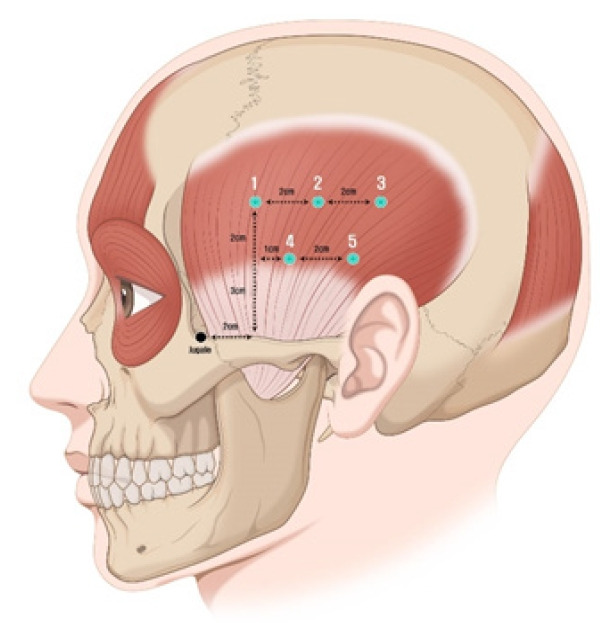

The initial instance of isolated unilateral temporalis muscle hypertrophy (IUTMH) was reported in 1990. Since then, only few cases have been documented. The cause of this condition remains ambiguous; however, it is presumed to be linked to compensatory and stress-induced hypertrophy. We introduce a rare case of the diagnosis and treatment of IUTMH. A 39-year-old woman presented with a steadily enlarging pain-free swelling on the left side of her face, first noticed a month ago. Apart from a hyperthyroidism medication regimen her medical history was unremarkable. She had no history of temporomandibular joint disease, bruxism, surgery, or trauma. However, she complained of having been under substantial stress lately. Contrast-enhanced magnetic resonance imaging revealed asymmetric temporalis muscle hypertrophy. The treatment plan consisted of administering type A botulinum toxin injections into left temporalis muscle, supplemented by lifestyle changes and relaxation techniques. At a follow-up visit 9 months after the injections, the muscle contour was normalized both in physical and in radiologic examinations. While further supportive evidence is needed, it can be anticipated that cosmetic treatment with botulinum toxin, rather than surgical interventions, will become the standard treatment of IUTMH.